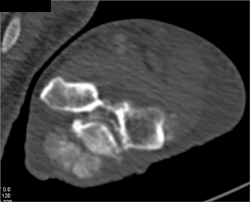

Myeloma